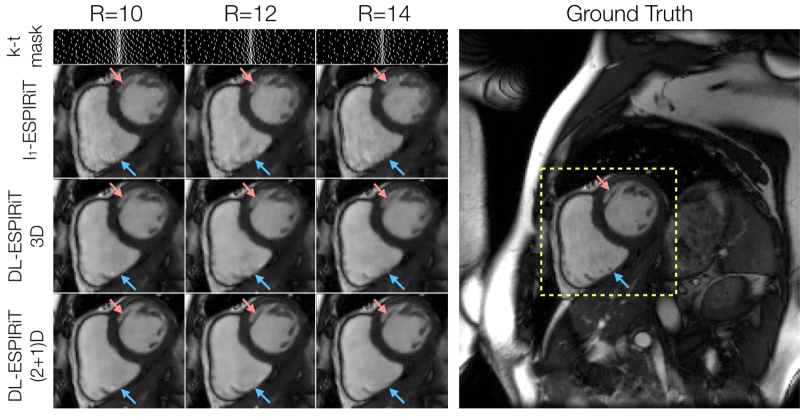

Figure 5 shows representative l1subscript𝑙1l_{1}-ESPIRiT, 3DM2 DL-ESPIRiT, and (2+1)DM2 DL-ESPIRiT reconstructions of data that was retrospectively undersampled by 12X. For this set of images, (2+1)DM2 DL-ESPIRiT is able to capture more realistic cardiac dynamics than l1subscript𝑙1l_{1}-ESPIRiT. l1subscript𝑙1l_{1}-ESPIRiT reconstructions show significant staircasing artifacts along time, which are characteristic of total variation-based reconstructions. Furthermore, error maps in Fig. 5 show that the (2+1)DM2 network produces higher fidelity images than both l1subscript𝑙1l_{1}-ESPIRiT and 3DM2 DL-ESPIRiT reconstructions. Corresponding videos depicting magnitude and error images are shown in Supporting Information Video S4. In Figure  6, the performance across all reconstruction methods for acceleration rates 10, 12, and 14 is compared. As the acceleration rate is increased, each method produces progressively blurrier images, except for the (2+1)DM2 DL-ESPIRiT reconstruction method, which retains sharpness of left ventricular trabeculae. A corresponding video showing reconstructions at each acceleration rate is shown in Supporting Information Video S5.

Figure 6: A fully-sampled dataset acquired on a 3.0T scanner is retrospectively undersampled by factors of 10, 12, and 14 using variable density masks. As expected, reconstructed mid-systolic frames become progressively blurrier as the acceleration rate is increased. This is particularly evident in smaller structures such as left ventricular trabeculations (red arrow). However, the (2+1)DM2 DL-ESPIRiT network retains sharpness of this structure as the acceleration rate is increased. However, none of the reconstruction methods were able to recover tiny papillary muscle structures inside of the right ventricle for this range of acceleration rates (blue arrows). Corresponding videos of reconstructions at each acceleration rate shown here are shown in Supporting Information Video S5.